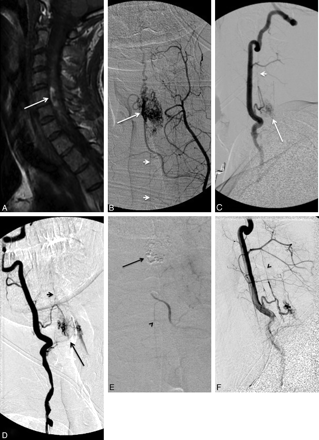

A, A 31-year-old patient presenting with quadriparesis secondary to intramedullary hemorrhage seen as hyperintensity in a sagittal T1-weighted MR image (arrow). B−D, The spinal angiograms show an intramedullary AVM (arrow) with arterial feeders from the ASA (arrowheads), which, at this level, is supplied by the right vertebral artery (C and D) and the left ascending cervical artery from the thyrocervical trunk (B). E, The AVM is embolized with n-BCA (arrow) with a microcatheter positioned via the left ascending cervical artery into the ASA branch feeding the nidus. Postembolization angiogram shows no residual supply to the nidus from the left ascending cervical artery, while the supply to the ASA is preserved (arrowhead). F, Postembolization right vertebral artery angiogram shows residual nidus (<30% of the total AVM nidus) and preserved flow into the ASA (arrowhead).